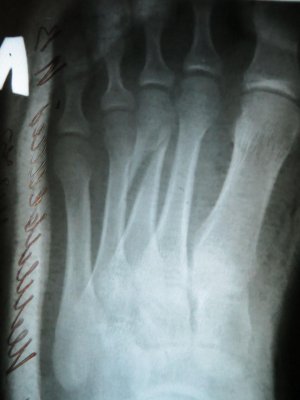

На следующий день повёз брата к целительнице, и заодно показал свою ногу. Она мне сказала, что там перелом. В травмпункте информация подтвердилась (сделали рентген который остался у врача). Оказалась сломана третья плюсневая кость, и мне просто наложили гипс прописали ОСТЕОГЕНОН (1т 2р/д).

Через неделю сделали повторный снимок, на котором я не заметил особых изменений, и наш травматолог для успокоения совести (по его словам) отправил меня на консультацию в больницу (решить вопрос о установки спицы).

Сегодняшний рентгеновский снимок прилагаю.